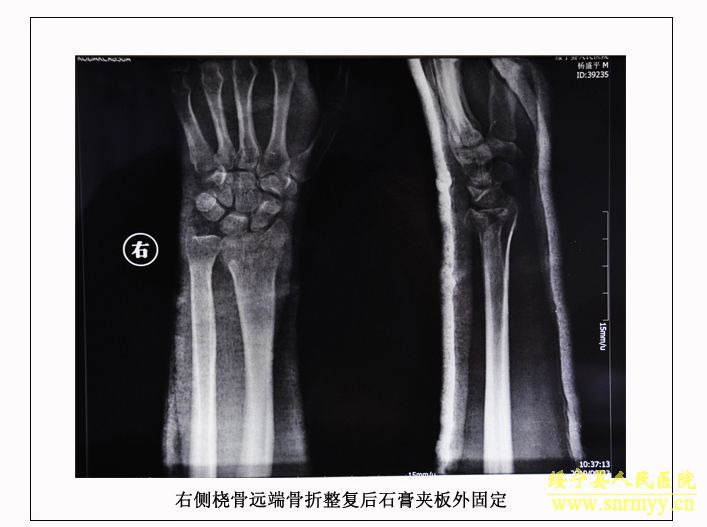

经检查:当时病人体温36.5℃、脉搏105次/分钟、呼吸25次/分钟、血压152/98mmhg,呈昏迷状,头面部、右手、左下肢均不同程度受伤,双侧瞳孔不等大,光反射消失;同时右手臂和左大腿均有骨折。GCS评分:仅4分,根据评分标准(轻度颅脑损伤为12—15分、中度为8—12分、重度为5—8分、极重度为3—5分)该病人属于极重度颅脑损伤。CT检查结果为脑干挫裂伤、双侧额叶、左颞叶、右顶叶脑挫裂伤、左侧颞部硬膜外、下血肿,左顶硬膜下血肿,蛛网膜下腔出血,脑室内积血,左侧额部下积液,左眼框内侧壁,枕骨骨折。X光片显示右桡骨粉碎性骨折,左股骨干骨折。诊断为:1、极重度颅脑损伤:(1)脑干挫裂伤。(2)双侧额叶、左颞叶、右顶叶脑挫裂伤。(3)右颞部硬膜外血肿。(4)外伤性蛛网膜下腔出血。(5)枕骨骨折。(6)头皮多处挫裂伤。2、右桡骨粉碎性骨折。3、左股骨干骨折。临床上如此严重的脑损伤死亡率极高,再加上合并多处骨折创伤,病人危在旦夕。